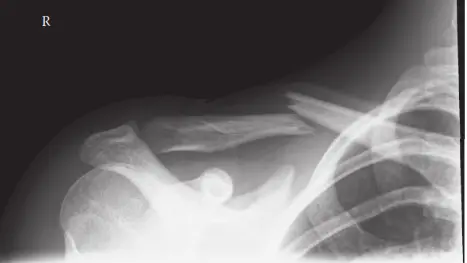

الأشعة السينية (X-rays):

- تُعد الأشعة السينية هي الفحص الأولي والأكثر شيوعاً. يتم التقاط صور متعددة من زوايا مختلفة، عادةً صورة أمامية خلفية (AP) وصورة بزاوية ميلان الرأس (cephalic tilt view) 30-45 درجة (تُعرف أيضاً بـ "منظر الصدفة" أو "serendipity view")، وقد تُطلب صور جانبية أيضاً.

- تساعد هذه الصور في تحديد نمط الكسر، درجة الإزاحة (مدى ابتعاد الشظايا عن بعضها)، وقصر العظم، ووجود أي تفتت.